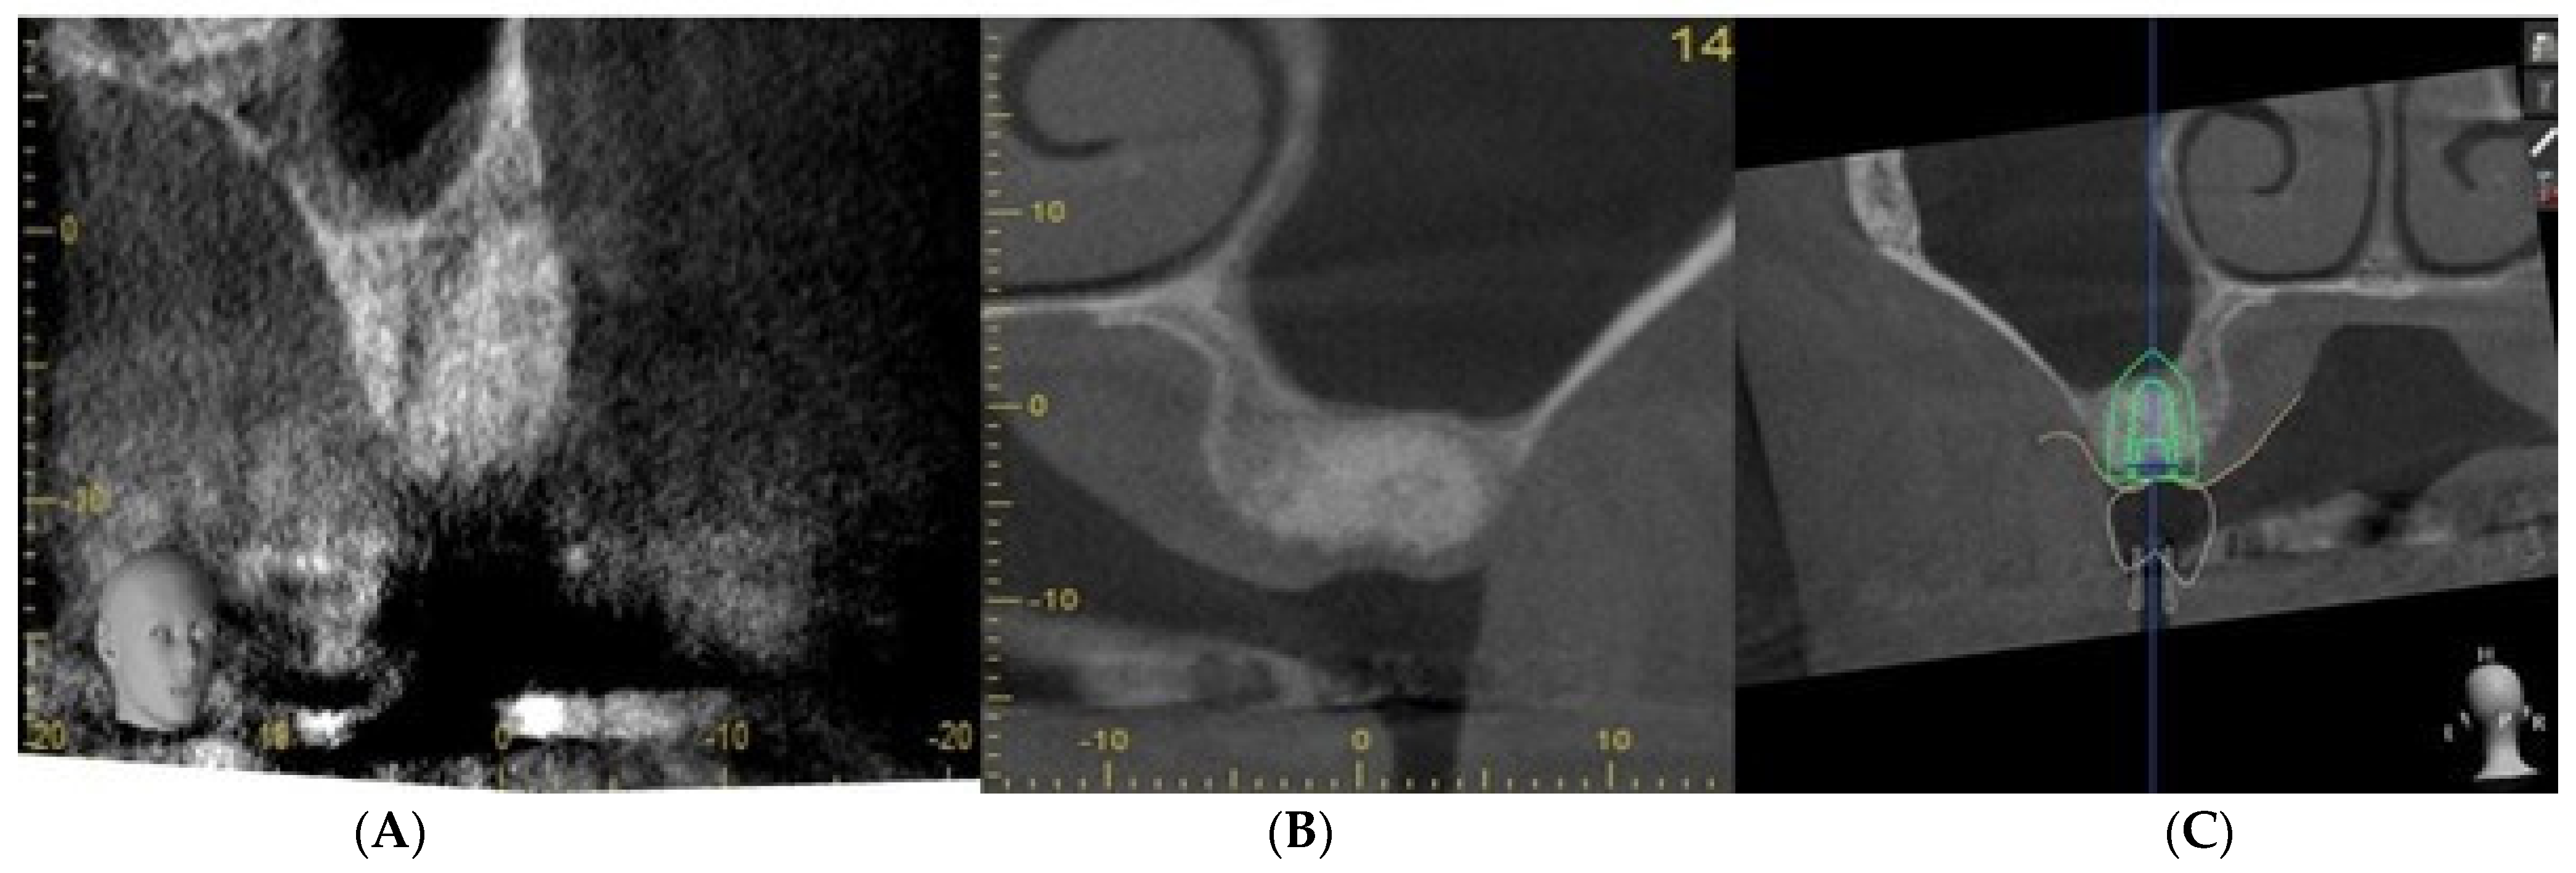

2.2. Case Study

| Step 1 | Assess alveolar ridge condition and morphology clinically and radiologically

|

| Step 2 | Extract using minimally invasive technique and clean and irrigate the extraction socket

| Step 3 | Augment and suture